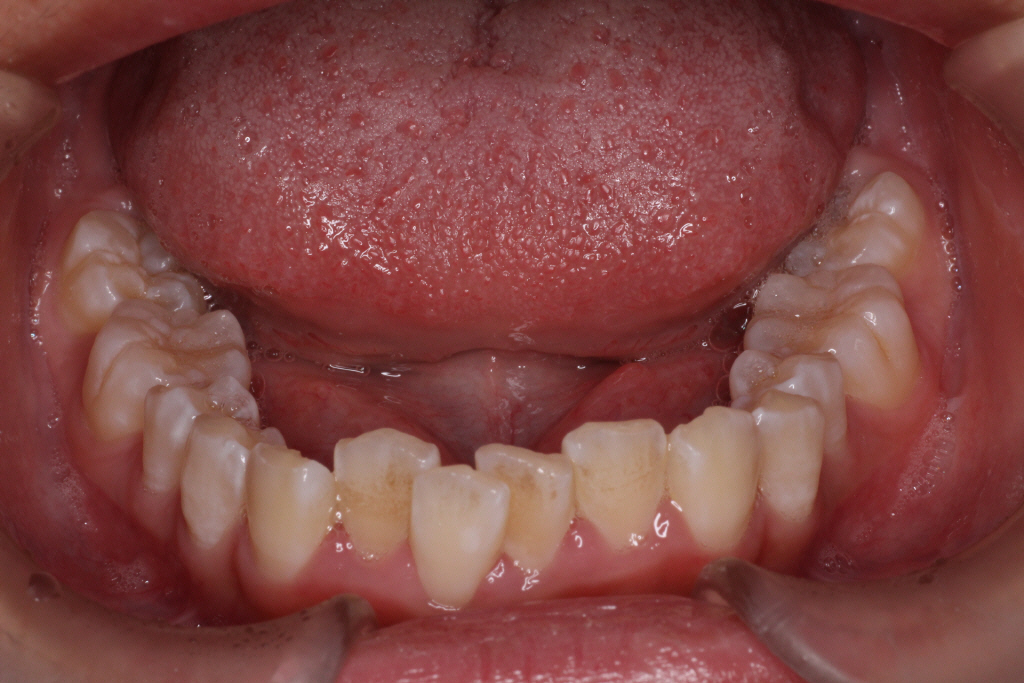

カリエールモーションが終わった時の口腔内写真です。

上の奥歯が後ろに下がったおかげで前歯には隙間ができています。

左の噛み合わせを見ると下の歯と歯の間に上の歯が入り込んでいることがわかります。

1歯対2歯の関係です。

右の噛み合わせを見ると左の噛み合わせより少し多めに奥歯を後ろに下げていることがわかります。

オーバーコレクションといって少し戻ることを想定して多めに動かしておくことを言います。